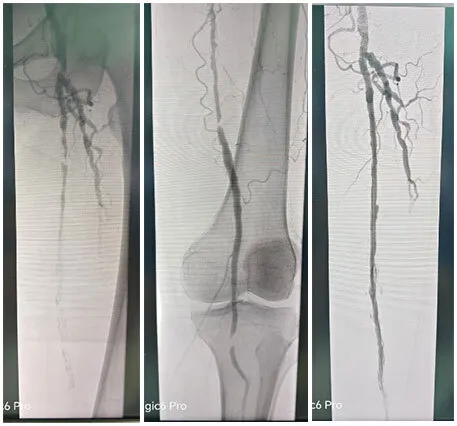

主诉åQšåŒä¸‹è‚¢é—´æ­‡æ€§è·›è¡ŒåŠòq´ã€?/p>

术å‰è¯Šæ–­åQšæœ¯å‰CTAæç¤ºåŒä¸‹è‚¢åŠ¨è„‰å×I漫èÊYæ–‘å—ã€é’™åŒ–æ–‘å—ã€æØœåˆæ–‘å—,½Ž¡è…”ä¸åŒ½E‹åº¦ç‹­çª„åQ›å³é«‚内动脉ã€å³è‚¡åŠ¨è„‰ã€åŒä¾§é¢ˆåŽåŠ¨è„‰ã€èƒ«å‰åŠ¨è„‰å±€éƒ¨é—­å¡žã€?/p>

手术˜q‡ç¨‹åQšæœ¯ä¸­é€ åª„½Cø™‚¡‹¹?è…?è†ä¸‹èŠ‚æ®µæ€§ç‹­½H„闭塞,多å‘é’™åŒ–ã€‚ä¿æŠ¤ä¼žä¸‹å‡å®¹ï¼Œä½†è¡€½Ž¡é’™åŒ–局部难以推˜q›ï¼Œå‡å®¹¾l“æŸåŽï¼Œäºˆä»¥¾U¦æŸåž‹è¯ç‰©çƒå›?*150mmã€?*200mm全程处ç†åQŒéž˜å†…造媄昄¡¤ºç‹­çª„ŒDµå®Œå…¨å¤é€šï¼Œå†…膜光整åQŒè¡€‹¹é€šç•…åQŒæœªè§é€ åª„å‰‚å¤–æ¸—ï¼Œæœªè§æ˜Žæ˜¾æ “å¡žã€‚æ‰‹æœ¯é¡ºåˆ©ï¼Œæœ¯åŽæ‚£è€…安˜q”ç—…æˆÑ€?/p>